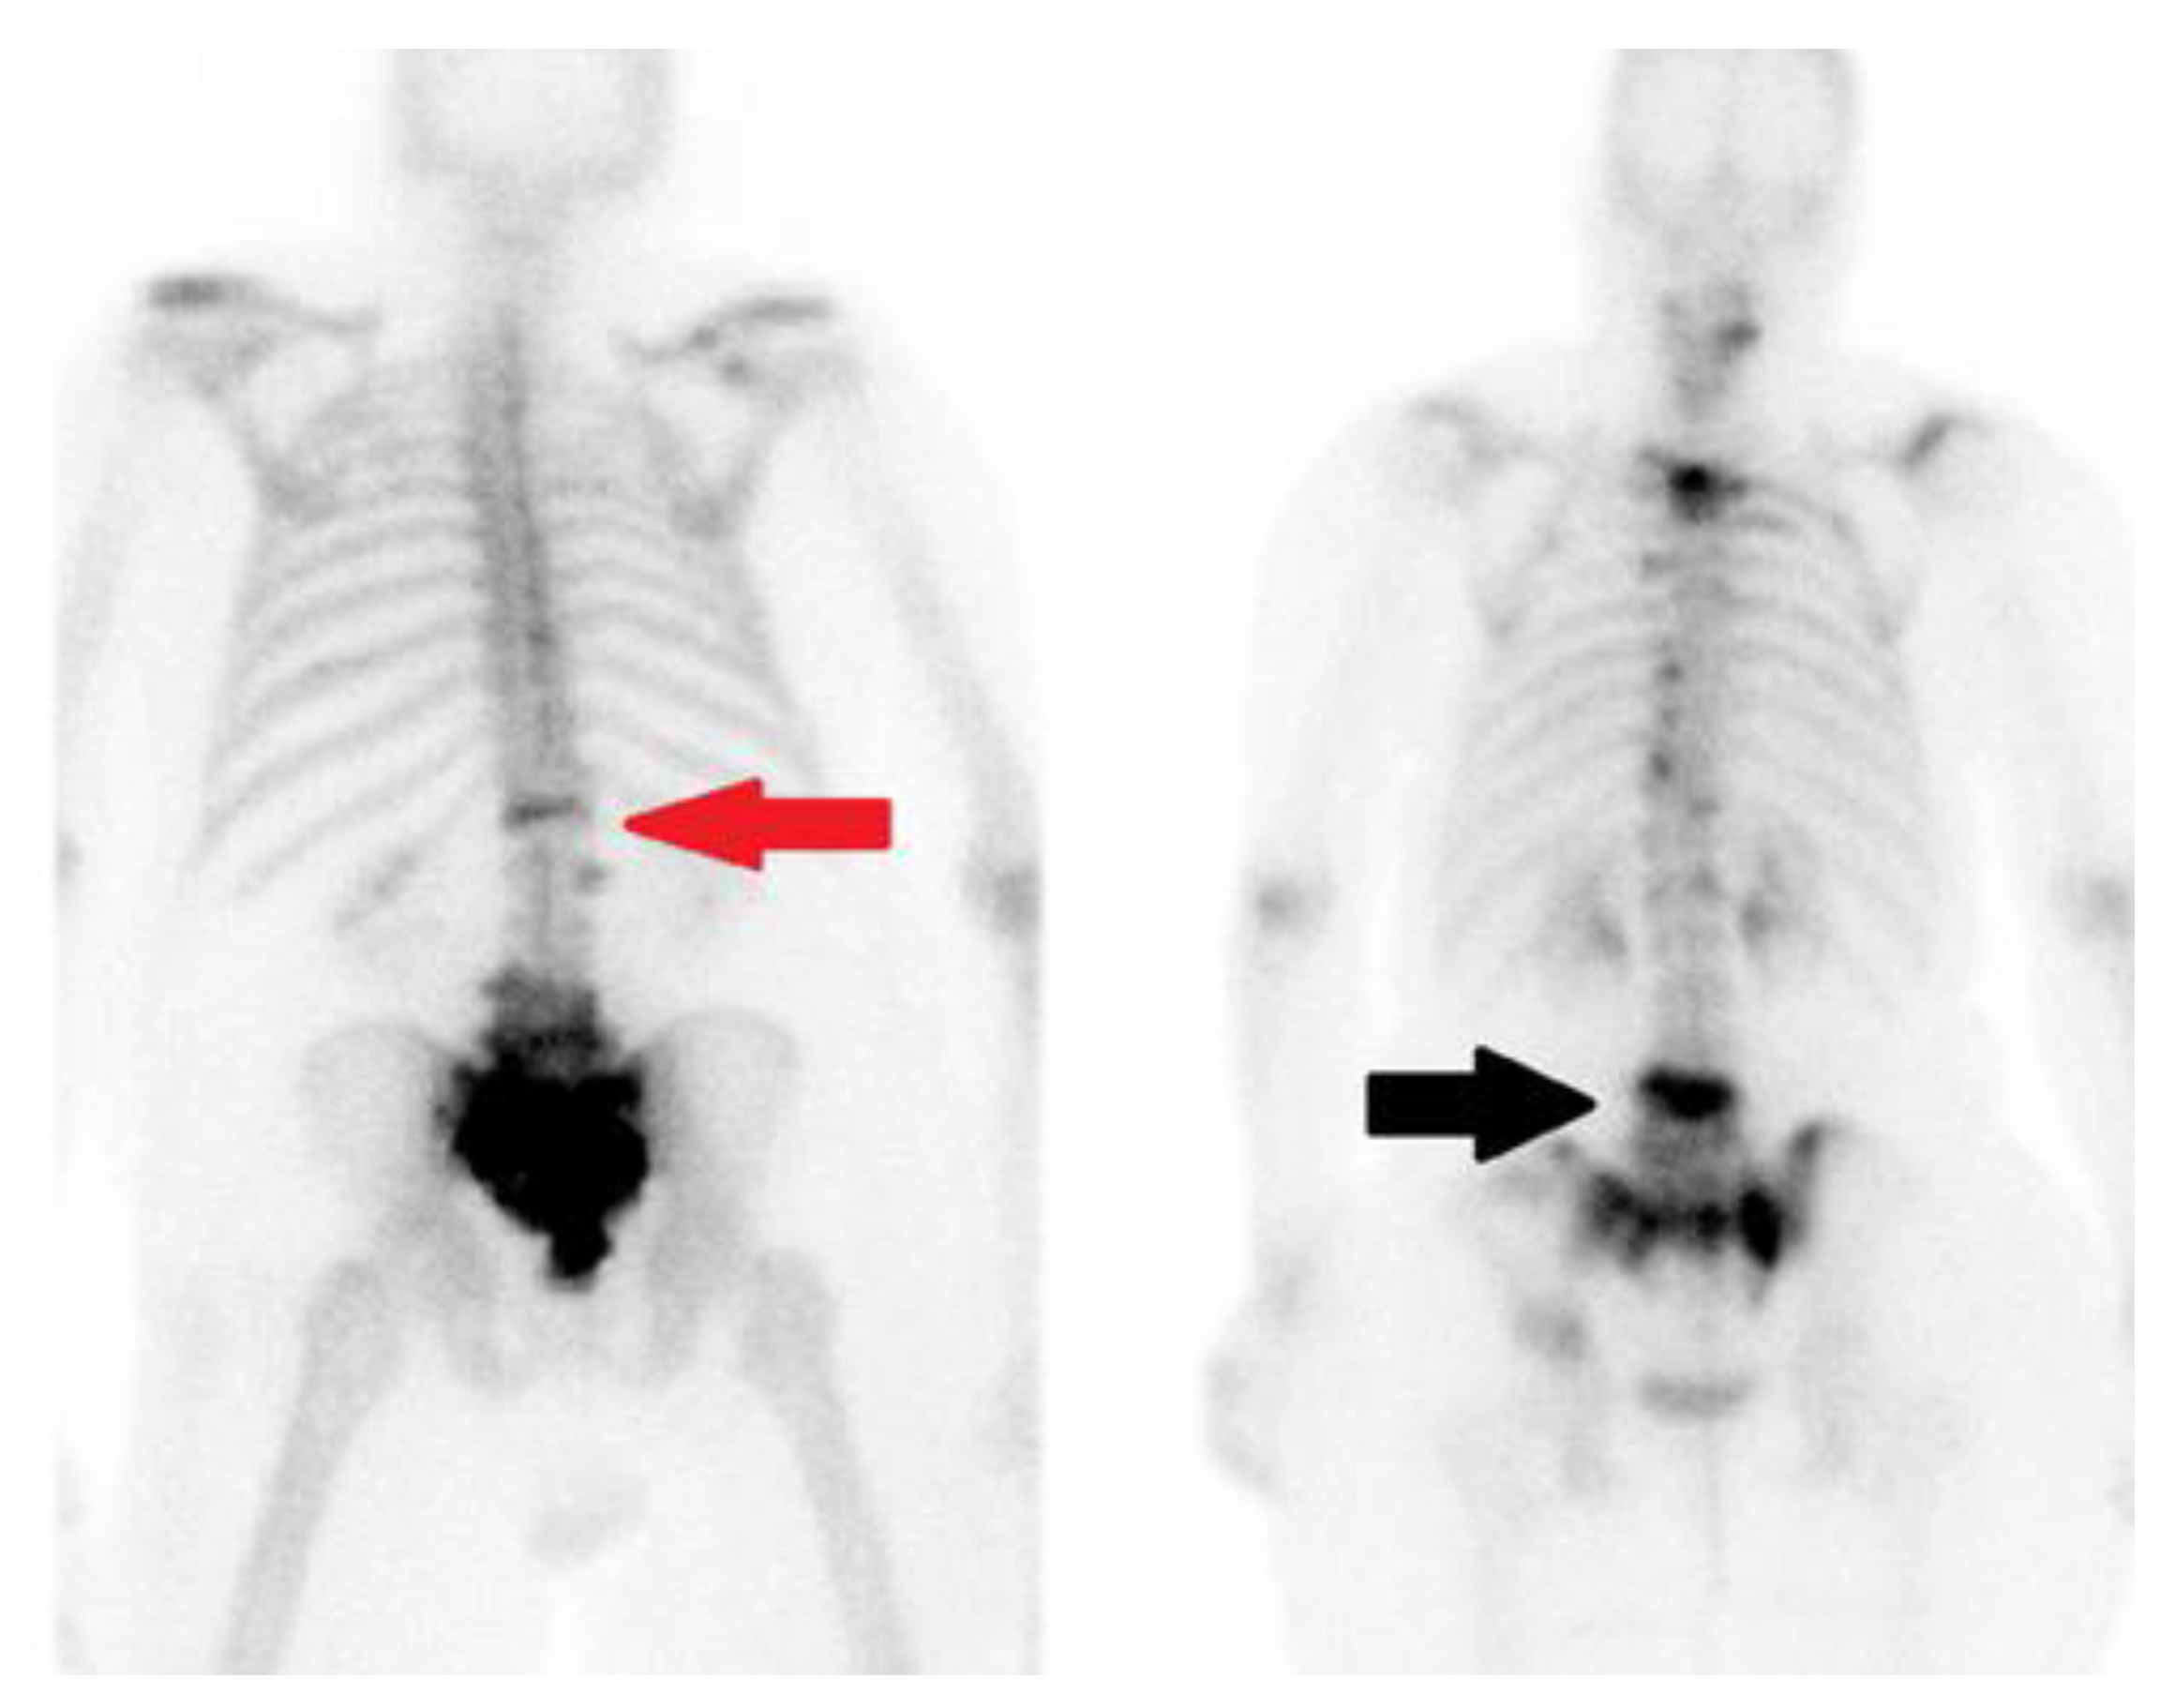

4.4. Nuclear Medicine

| PET and Bone Scan | Detects metabolic activity and useful in identifying metastatic disease or infection, detects increased bone activity |